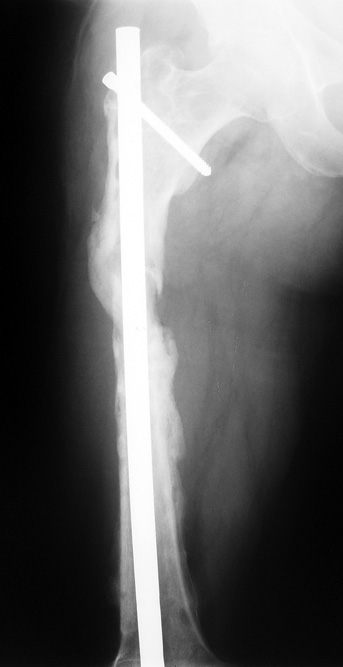

Eksternal fiksatör ile geçen süre (eksternal fiksasyon indeksi), gereken distraksiyon miktarına bağlıdır ve bu süre boyunca bazı komplikasyonlarla karşılaşılabilir. Distraksiyon dönemi sona erdikten sonra, distraksiyon süresinin iki katını aşan konsolidasyon döneminde hastalar eksternal fiksatörü zorlukla tolere edebilirler. Yeterli konsolidasyon sağlanmadan eksternal fiksatör çıkartılırsa ise kırıklar, deformite ve kısalık oluşabilir. Hastanın fiksatör ile birlikte geçirdiği sürenin azaltılması ve böylece hasta konforunun ve aktivite düzeyinin arttırılması için intramedüller çivi üzerinden uzatma yöntemi uygulanmaktadır. Bu yöntemde distraksiyon dönemi sona erdiğinde kemiğin içindeki çivi statik olarak kilitlenmekte ve eksternal fiksatör çıkartılmaktadır. Stabilizasyon intramedüller çivi tarafından sağlandıktan sonra konsolidasyon dönemi gerçekleşmektedir. Bu şekilde hem eksternal fiksatörün uzun süre kalmasından hem de erken çıkartılmasından kaynaklanan komplikasyonların önüne geçilmektedir.

Vaka 2